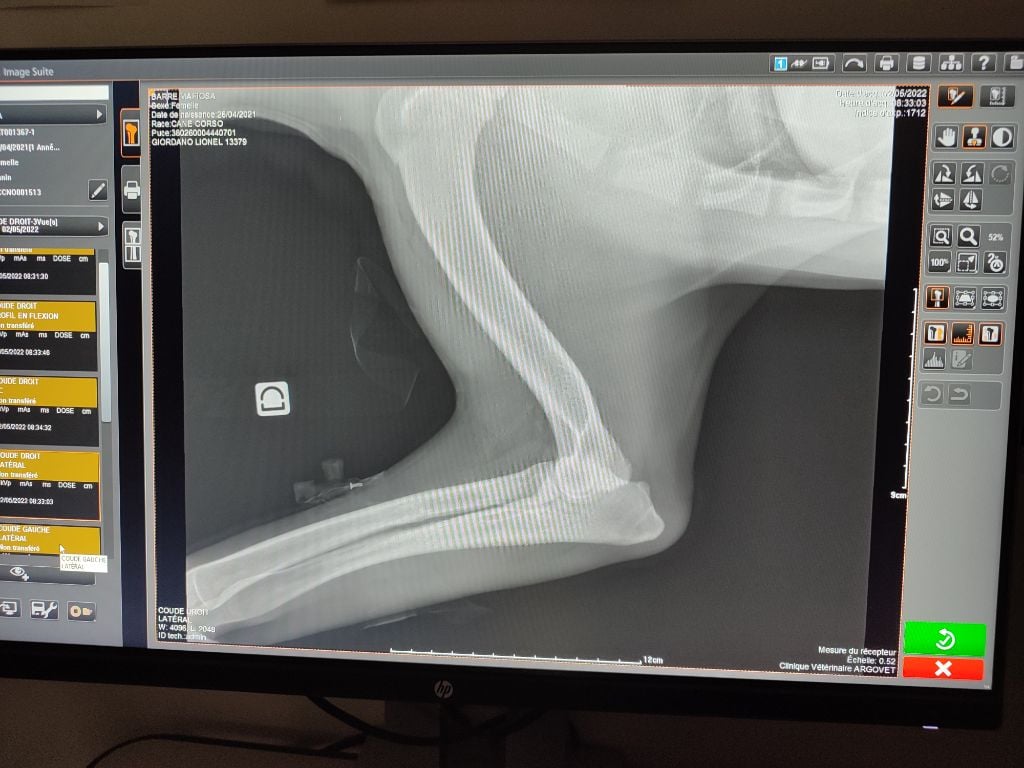

| Couleur | noire ADN HD C / ED 0/ DSRA N/N |